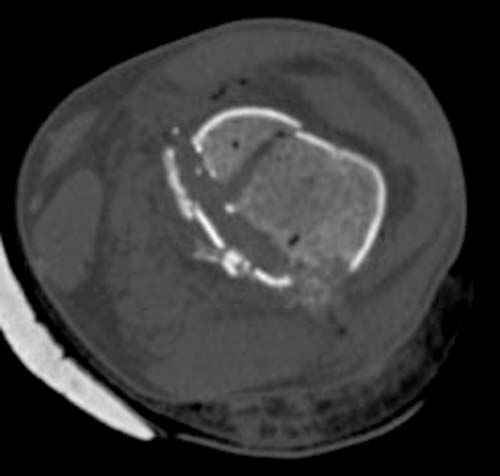

По Густило и Андерсену все high-energy переломы являются III не зависимо от степени повреждения мягких тканей. Plating такого перелома на второй день кажется немного рискованным хотя "победителей не судят". Судя по КТ, медиальный мыщелок стабильный, насколько необходимо было его фиксировать?

Идеальная репозиция?! -На снимочке A-P проeкции видна "зазубрина" по суставной поверхности, латеральный снимок - тоже не идеально.

Множество мелких FB в кости.